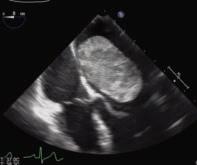

e answer came with the last test: an echocardiogram. Mason looked at the screen. “I saw this mass, it looked like a big old kidney bean in my le ventricle.”

e imaging had captured a large tumor inside her heart. e Kaiser Permanente cardiologist recognized that he was dealing with an unusual and potentially deadly cause of faint-

ing and immediately referred Mason to Emory cardiac surgeon Douglas Murphy at Emory Saint Joseph’s Hospital.

e ndings on the echocardiogram were classic for an atrial myxoma, says Murphy—a benign tumor that can arise in any chamber of the heart. “ e tumor on Ms. Mason’s heart had grown so large that in certain positions, it could greatly diminish forward blood ow,” he says.

ese tumors are also dangerous because small pieces can break o and enter the bloodstream, causing stroke. “Surgical removal is usually performed urgently,” Murphy says.

Mason was promptly admitted to Emory Saint Joseph’s and, on June 6, underwent an endoscopic robotic removal of the tumor, which was the size of a small potato and located in front of the mitral valve. It was taken out through ve small incisions in the right side of her chest.

Murphy and his colleagues have removed more than 200 cardiac tumors using robotics over the last 16 years. Such surgery is less invasive than traditional surgery, with a shorter recovery time.

“Surgery went very well, and Ms. Mason went home a er three days,” Murphy says.